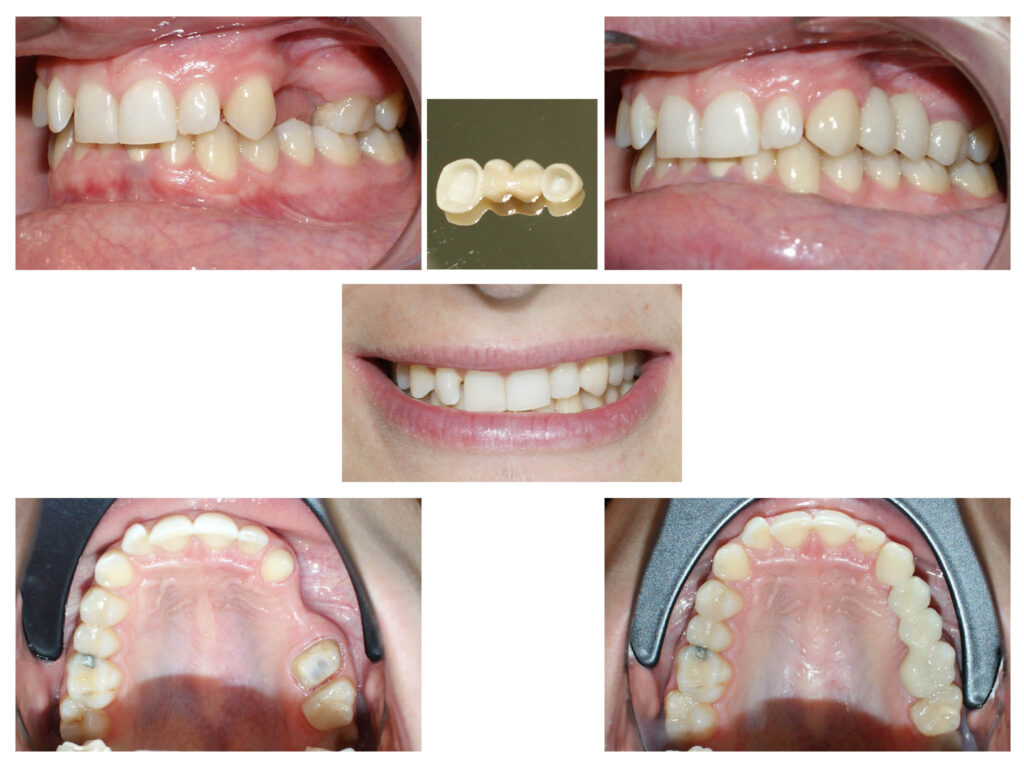

#anodonție #dinte nanic #aparat ortodontic #implante dentare